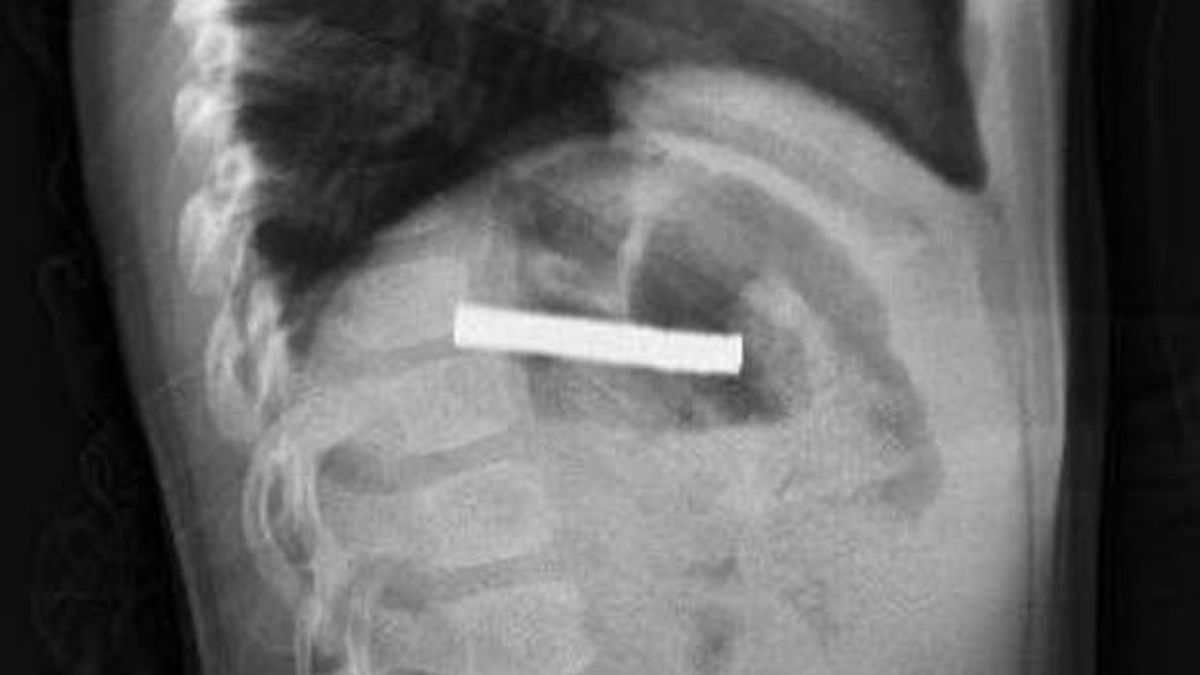

Türkiyədə 3 yaşlı uşağın boğazından 19 ədəd maqnit çıxarılıb.

Medicina.az xəbər verir ki, Ərzurumda uşaq evdə tapılan 19 maqniti udub.

Fırat Universitetinin Uşaq Qastroenterologiyası, Hepatologiya və Qidalanma kafedrasının müdiri Prof.Dr.Yaşar Doğan endoskopik üsulla uşağın qida borusuna ilişib qalmış 19 maqniti çıxarıb.

Maqnitlər uzun müddət qida borusunda ilişib qalıb, yemək borusu və mədə girişində zədələr yaranıb.